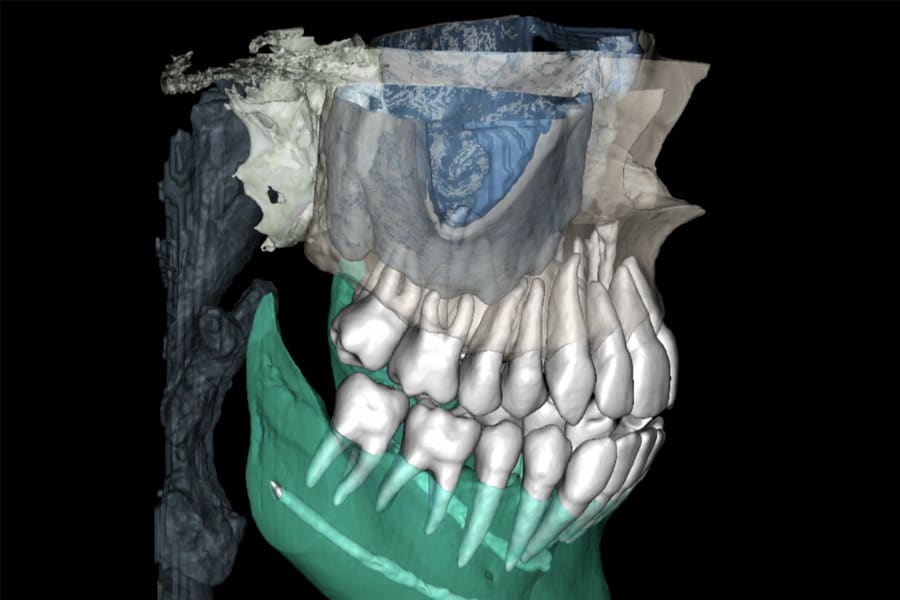

Posterior intrusion (eg, approximately 2 mm to 3 mm molar intrusion) is modeled to define mandibular CCW autorotation, ensuring acceptable anterior guidance and envelope. Hybrid analog/digital or fully digital jaw-tracking/axiography improves precision for the terminal mandibular position at treatment completion.9-11 (Figure 10 through Figure 13)